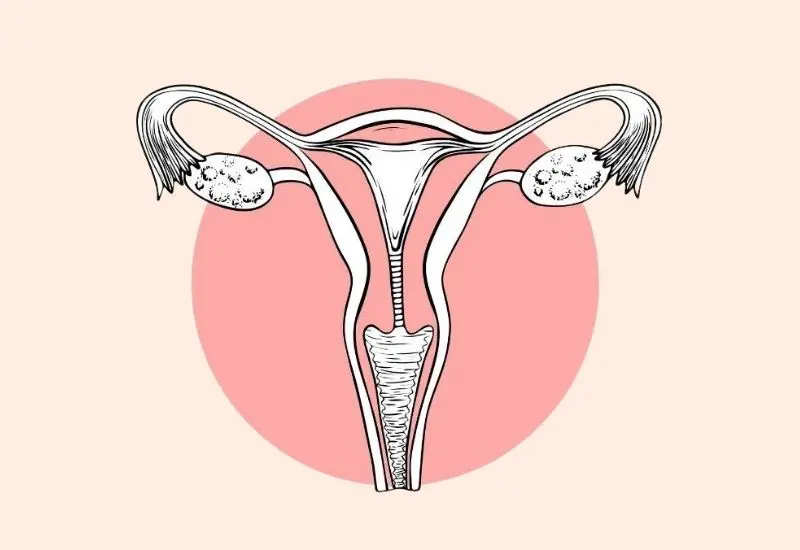

Understanding ovarian hyperstimulation syndrome (OHSS) is crucial for anyone undergoing fertility treatments. This condition can turn the excitement of IVF into a nightmare. While some women experience mild symptoms of ovarian activity, others face severe complications like ovarian cysts and ovarian enlargement that require medical attention to cause. Recognizing the signs early can make all the difference.

Ovarian hyperstimulation syndrome (OHSS) is a condition that occurs when the ovaries respond excessively to fertility medications. These medications stimulate the ovaries to produce multiple eggs. This overreaction can lead to serious complications.

Hormonal Imbalance

During fertility treatments, hormonal changes trigger ovarian activity. Medications like gonadotropins increase hormone levels. This leads to enlarged ovaries and the formation of ovarian cysts during fertility treatment. The ovaries become swollen due to fluid buildup. This fluid can leak into the abdominal cavity, causing discomfort and other issues.